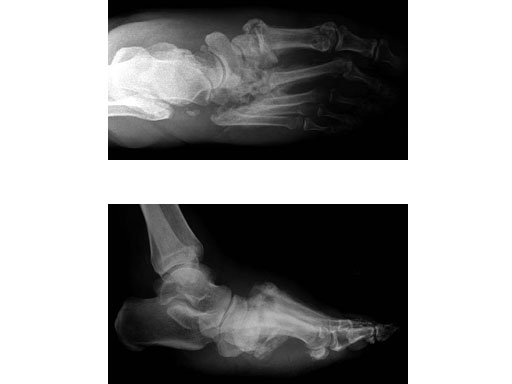

Case 2: 48-year-old male

Case provided by Andrew K Sands, New York, USA

Charcot foot treated with MFB and X-plate.